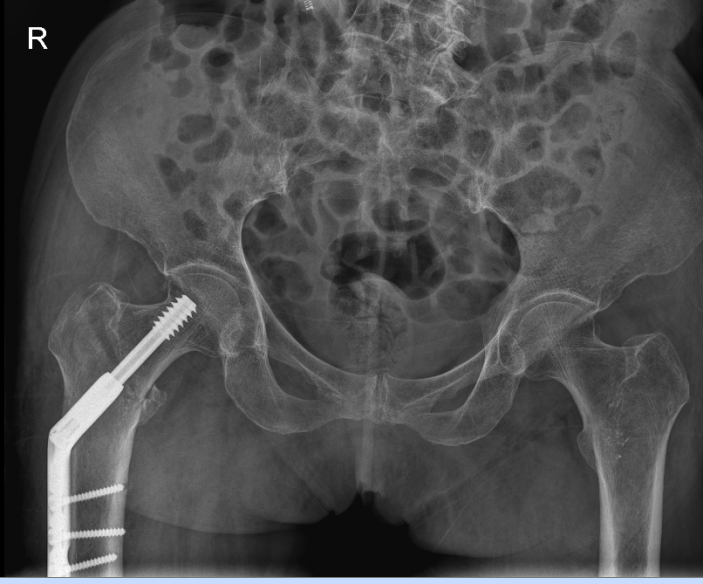

△右側(R)是賴婆婆3年前跌斷股骨術後,左側是本次手術術後。

10月20日,老人家被送進了手術室行左側人工股骨頭置換術。吳主任根據方案按部就班地實施手術,娴熟地完成每一個手術步驟,精心地把控每一個細節,确保髋部良好的活動性和穩定性,以及雙下肢等長。整個手術過程非常流暢、一氣呵成。術中患者各項生命體征平穩,術後平安返回病房。